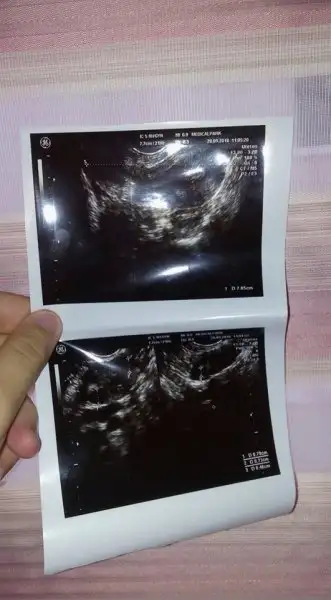

Canim ultrason goruntusunden anliyormusun birsey gostersem

Goster canim ama inan takinti yapiyorsun.cok kurcalama olan sagligini da bozacaksin.bende de akinti ve yanma problemi var gecmiyor.bu arada ben cokmsukur cok kolay hamile kaldim hatta egrafomdakiler bile sasirdi evlenir evlenmez oyoe diyim.merak etme sende de bisey yok.

Eklentiler

• 43308166_699596763749509_3263591823976693760_n.webp

43308166_699596763749509_3263591823976693760_n.webp

16,1 KB · Görüntüleme: 35

Cnm bazı yumurtalıklarda pko gorunumu olabılırmıs ama onemlı olan belırtısıymıs eger adet olamama tuylenme kılo artısı kısırlık problemi varsa onemlıymıs aynısı bendede oldu usg doktoru pko dedi ve yumurtalıgın sişmiş dedi hemen jınekologa gıttım onemlı olan belırtı bısey yok dedi ayrıca pko doğuştan oluyo dıye bılıyorum

Adet oluyorum 29 gunde ve saati saatine killanmam sivilcem yok öyle sadece sonrada kanamam azaldi kafama takildi